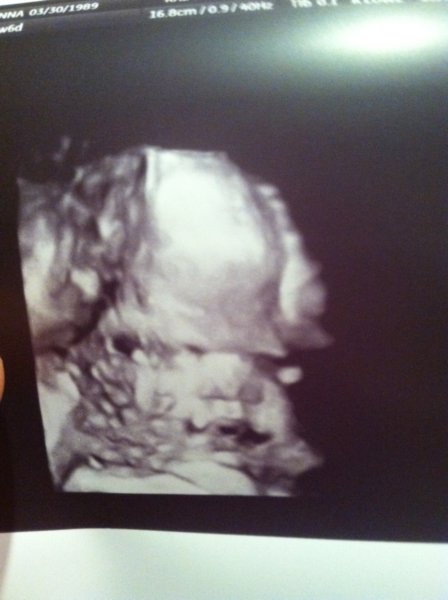

IMG_0335